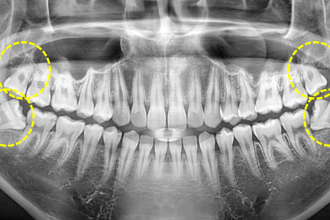

사랑니발치

굿프렌즈 치과 임상 케이스